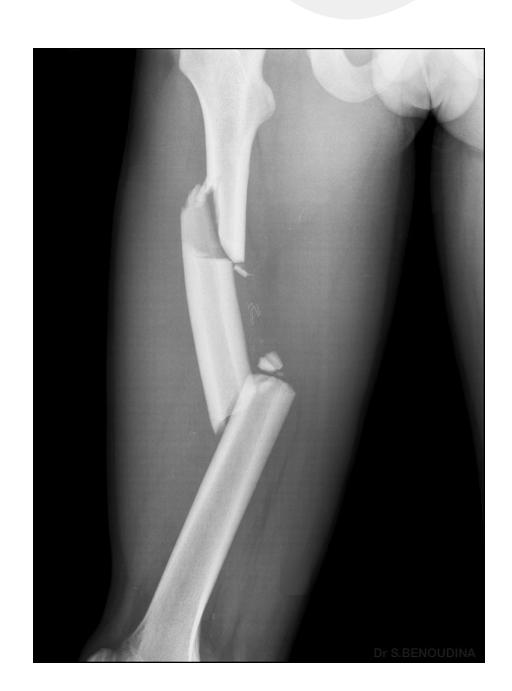

Femoral Shaft Fracture

Diagnosis: Femoral shaft fracture Management:

- IV line, fluids, blood transfusion

- 2 views and 2 joints x-rays (must see hip joint)

- Treatment of choice: Locked intramedullary nail